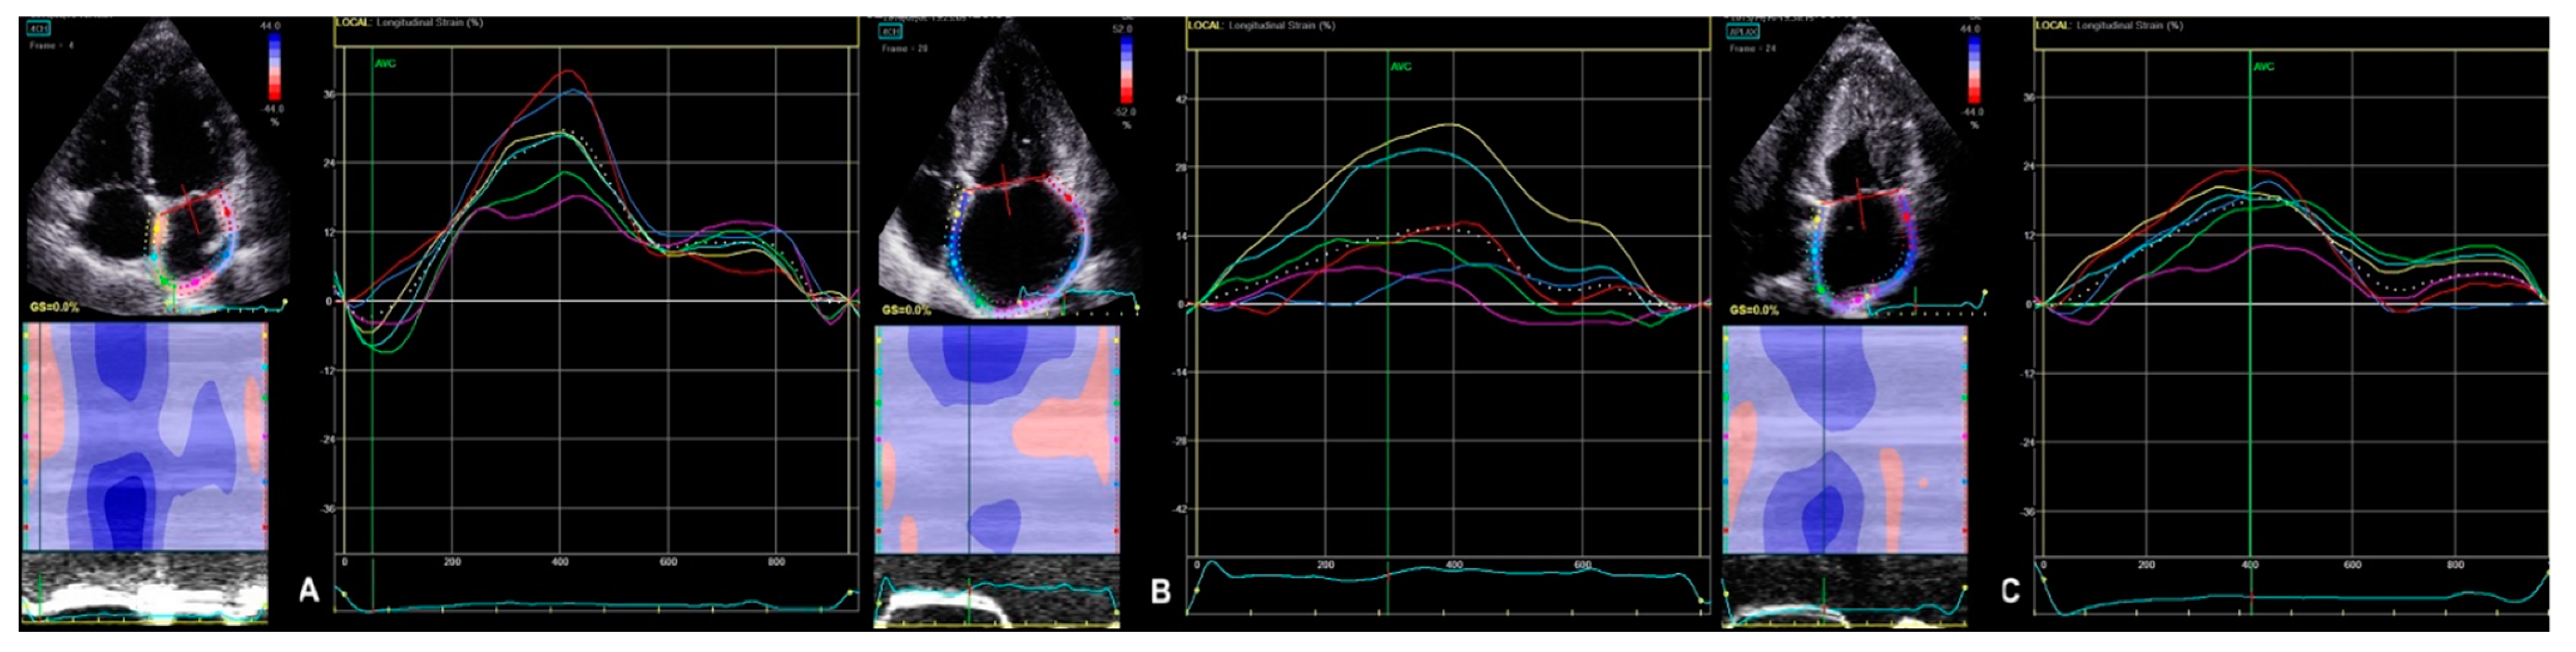

2.2.2. 2D STE Parameters

| 2D LV GLS | −15.2 (−17.5–−12.1) | −19.6 (−20.9–−17.9) | <0.000 | −12.4 (−14.2–−10.0) | −16.3 (−19.1–−13.9) | <0.003 | <0.000 | <0.001 |

| 3D LV area strain | −23.0 (−26.5–−21.0) | −26.5 (−28.8–−20.0) | 0.109 | −19.5 (−20.8– −17.5) | −25.0 (−27.0–−22.0) | <0.009 | <0.015 | 0.282 |

| 3D LV radial strain | 35.0 (29.5–42.5) | 39.5 (−29.0–−46.8) | 0.146 | 27.7 (24.8– −30.3) | 37.0 (32.0–−44.0) | <0.006 | <0.011 | 0.364 |